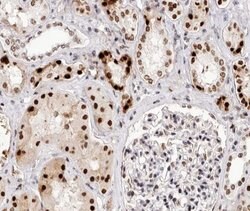

Antibody detects endogenous levels of Bcl-2 only when phosphorylated at Threonine 69.

| Applications | Immunohistochemistry (Paraffin), Western Blot, Immunocytochemistry |